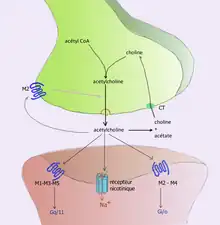

For example, acetylcholine is eliminated by having its acetyl group cleaved by the enzyme acetylcholinesterase; the remaining choline is then taken in and recycled by the pre-synaptic neuron to synthesize more acetylcholine.[9] Other neurotransmitters are able to diffuse away from their targeted synaptic junctions and are eliminated from the body via the kidneys, or destroyed in the liver. Each neurotransmitter has very specific degradation pathways at regulatory points, which may be targeted by the body's regulatory system or medication. Cocaine blocks a dopamine transporter responsible for the reuptake of dopamine. Without the transporter, dopamine diffuses much more slowly from the synaptic cleft and continues to activate the dopamine receptors on the target cell.[10]

- Acetylcholine was the first neurotransmitter discovered in the peripheral and central nervous systems. It activates skeletal muscles in the somatic nervous system and may either excite or inhibit internal organs in the autonomic system.[14] It is distinguished as the transmitter at the neuromuscular junction connecting motor nerves to muscles. The paralytic arrow-poison curare acts by blocking transmission at these synapses. Acetylcholine also operates in many regions of the brain, but using different types of receptors, including nicotinic and muscarinic receptors.[23]

| Botulinum Toxin (Botox) | Acetylcholine | – | Antagonist | Blocks Acetylcholine release in PNS

Prevents muscle contractions |

| Black Widow Spider Venom | Acetylcholine | – | Agonist | Promotes acetylcholine release in PNS

Stimulates muscle contractions |

| Neostigmine | Acetylcholine | – | – | Interferes with acetylcholinerase activity

Increases effects of ACh at receptors Used to treat myasthenia gravis |

| Nicotine | Acetylcholine | Nicotinic (skeletal muscle) | Agonist | Increases ACh activity

Increases attention Reinforcing effects |

| d-tubocurarine | Acetylcholine | Nicotinic (skeletal muscle) | Antagonist | Decreases activity at receptor site |

| Curare | Acetylcholine | Nicotinic (skeletal muscle) | Antagonist | Decreases ACh activity

Prevents muscle contractions |

| Muscarine | Acetylcholine | Muscarinic (heart and smooth muscle) | Agonist | Increases ACh activity

Toxic |

| Atropine | Acetylcholine | Muscarinic (heart and smooth muscle) | Antagonist | Blocks pupil constriction

Blocks saliva production |

| Scopolamine (Hyoscine) | Acetylcholine | Muscarinic (heart and smooth muscle) | Antagonist | Treats motion sickness and postoperative nausea and vomiting |